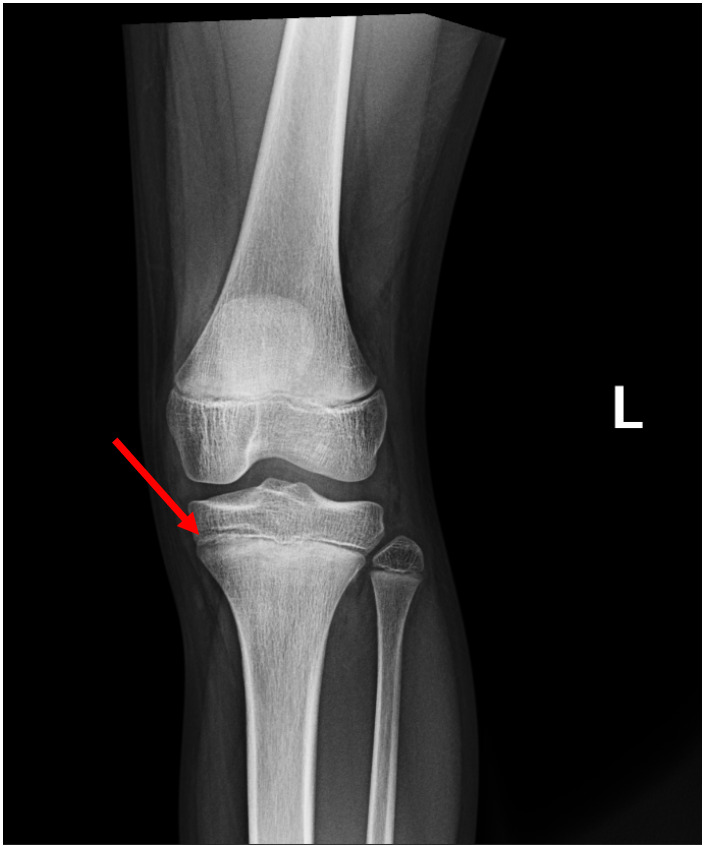

A 10-year-old female came into the emergency department (ED) after complaining about atraumatic knee pain and pressure. The patient had been very active, ran daily, and was slender. She was not unwell in any way and denied any fever, chills, chest pain, shortness of breath, headaches, or urinary problems. A physical examination was conducted and the following signs were found: pulse oximetry levels of 99% on room air, body temperature of 98.0 degrees, a pulse rate of 101 beats per minute, a respiratory rate of 18 breaths per minute, and significant pain at the tibial tubercle. Due to the tenderness of the patella, an X-ray of the knee was ordered. The knee radiograph demonstrated a small growth at the tibial tubercle (Figures 1 and 2). This growth was pressing against the shinbone and was the likely cause of pain for the patient.